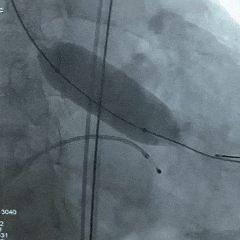

手术过程

根部造影:可见瓣叶钙化,几乎无反流

20mm球囊扩张,无腰,球囊轻微滑动

瓣膜系统定位

瓣膜展开后造影评估,深度可,无明显瓣周漏

多角度造影评估:瓣膜深度形态合适,冠脉灌注良好

脱钩后造影:瓣膜无位移,同轴性良好,无瓣周漏

术后超声测量

即刻瓣口流速2.2m/s;平均压差9mmHg,手术结束